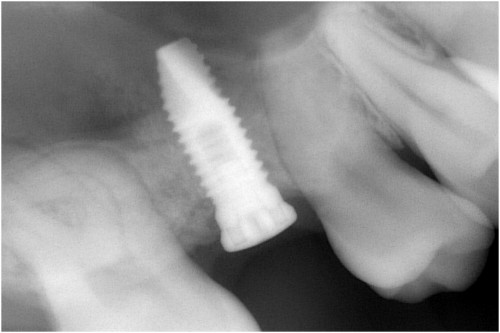

インプラント挿入